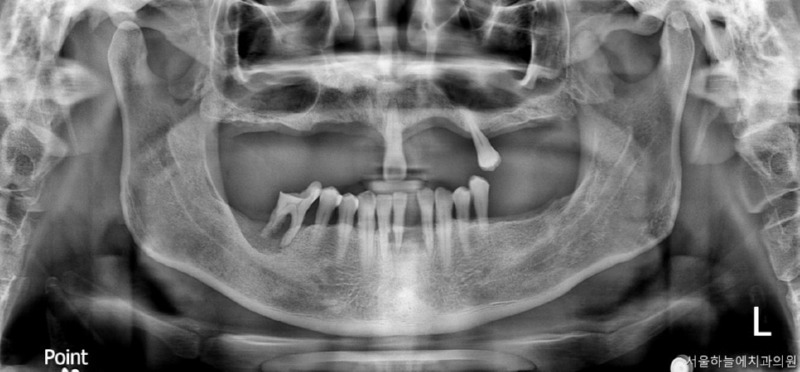

당뇨·고혈압을 모두 가지고 계셨던

전악 임플란트 케이스

이번에 소개해드릴 환자분은

당뇨와 고혈압, 두 가지 전신질환을

모두 가지고 계셨던 분으로

치아 결손이 광범위해

전악 임플란트가 필요한 상황이었습니다.

· 상악은 잇몸뼈가 매우 얇고 치아가 거의 남아 있지 않은 상태

· 하악은 부분 결손과 앞니의 심한 동요

· 식사가 어려울 정도로 기능 저하가 심한 상태